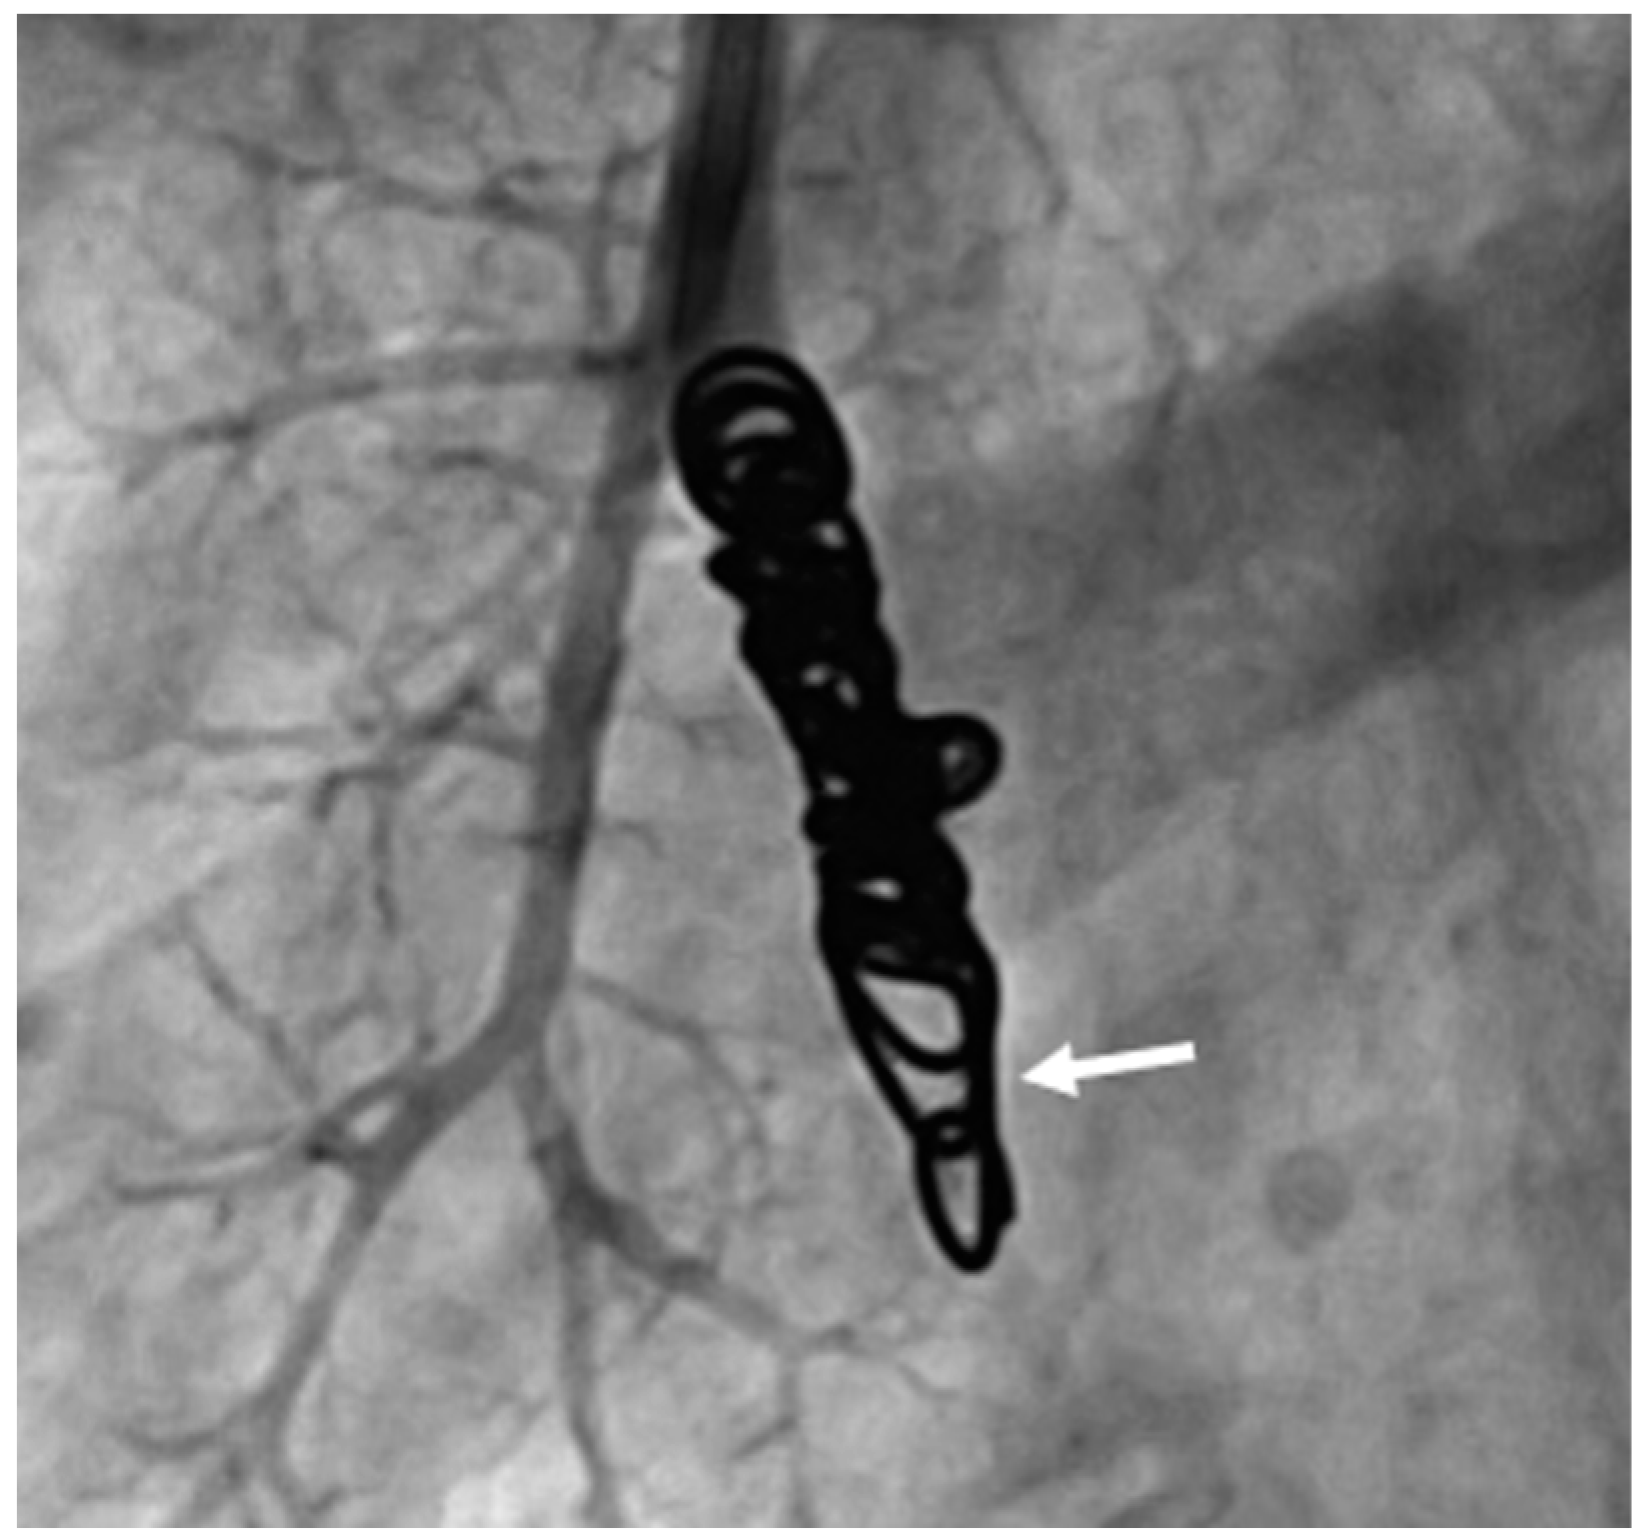

3.9. Evaluation of Recanalized Feeding Arteries with Regard to the Cause of Reperfusion

Furthermore, angiography images were examined for possible causes of reperfusion during re-embolization. In a total of 64 recanalized AV shunts, recanalization could be attributed to inadequate packing density of the implanted coils in 52 feeding arteries. Two examples are shown in Figure 7. In 15 of the 52 recanalized feeding arteries, we can further see a positioning of the embolization material on the wall of the vessel but not in the center (Figure 8).

Figure 7. Presentation of two PAVM with insufficient packing density of implanted coils.